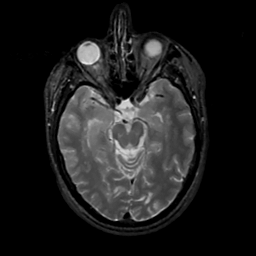

MR Study #2, February 17, 1991 -- Slice #19

[Home][Help][Clinical][Tour 1][Tour 2] Slice 19